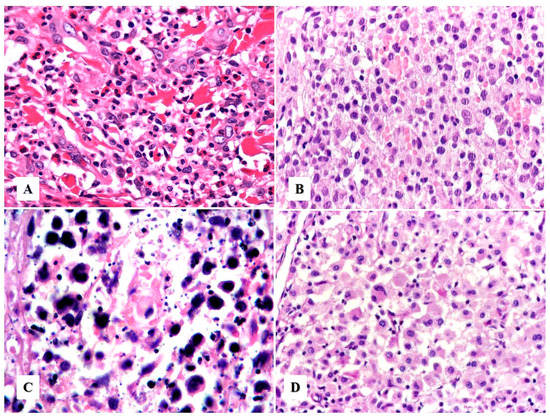

Morphologic Variants of Primary Cutaneous ALCL